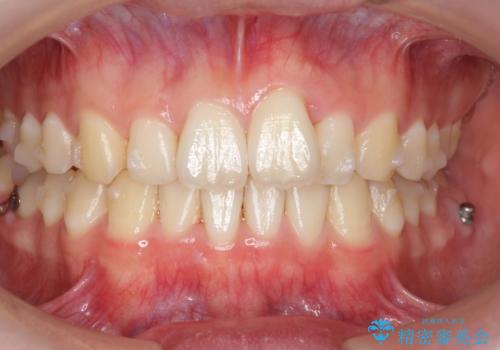

- マウスピース矯正

- 1年10ヶ月

奥歯を後ろに移動させるために、矯正用のミニスクリューを用いました。(インプラント矯正)